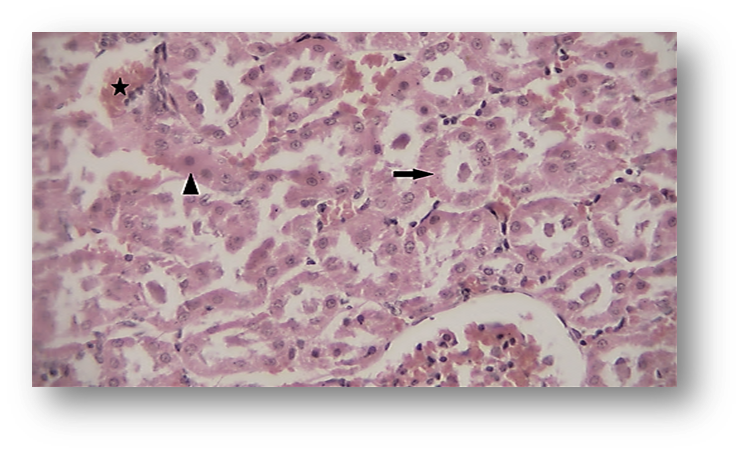

Likewise, renal histopathological evaluation (Fig. 5 and Fig. 8) showed a significant increase in necrosis, hyperemia, and cell swelling in the second group (ACR) compared to the control group. Betaine treatment in the third group was found to be significantly effective in mitigating renal pathological observations induced by ACR compared to Group 2.

Figure 8. Photomicrograph of Observed Renal Histopathological Features (Hematoxylin and Eosin [H&E],×400) in the Acrylamide (ACR)-Treated Group. Hyperemia (star) and necrosis (arrows).